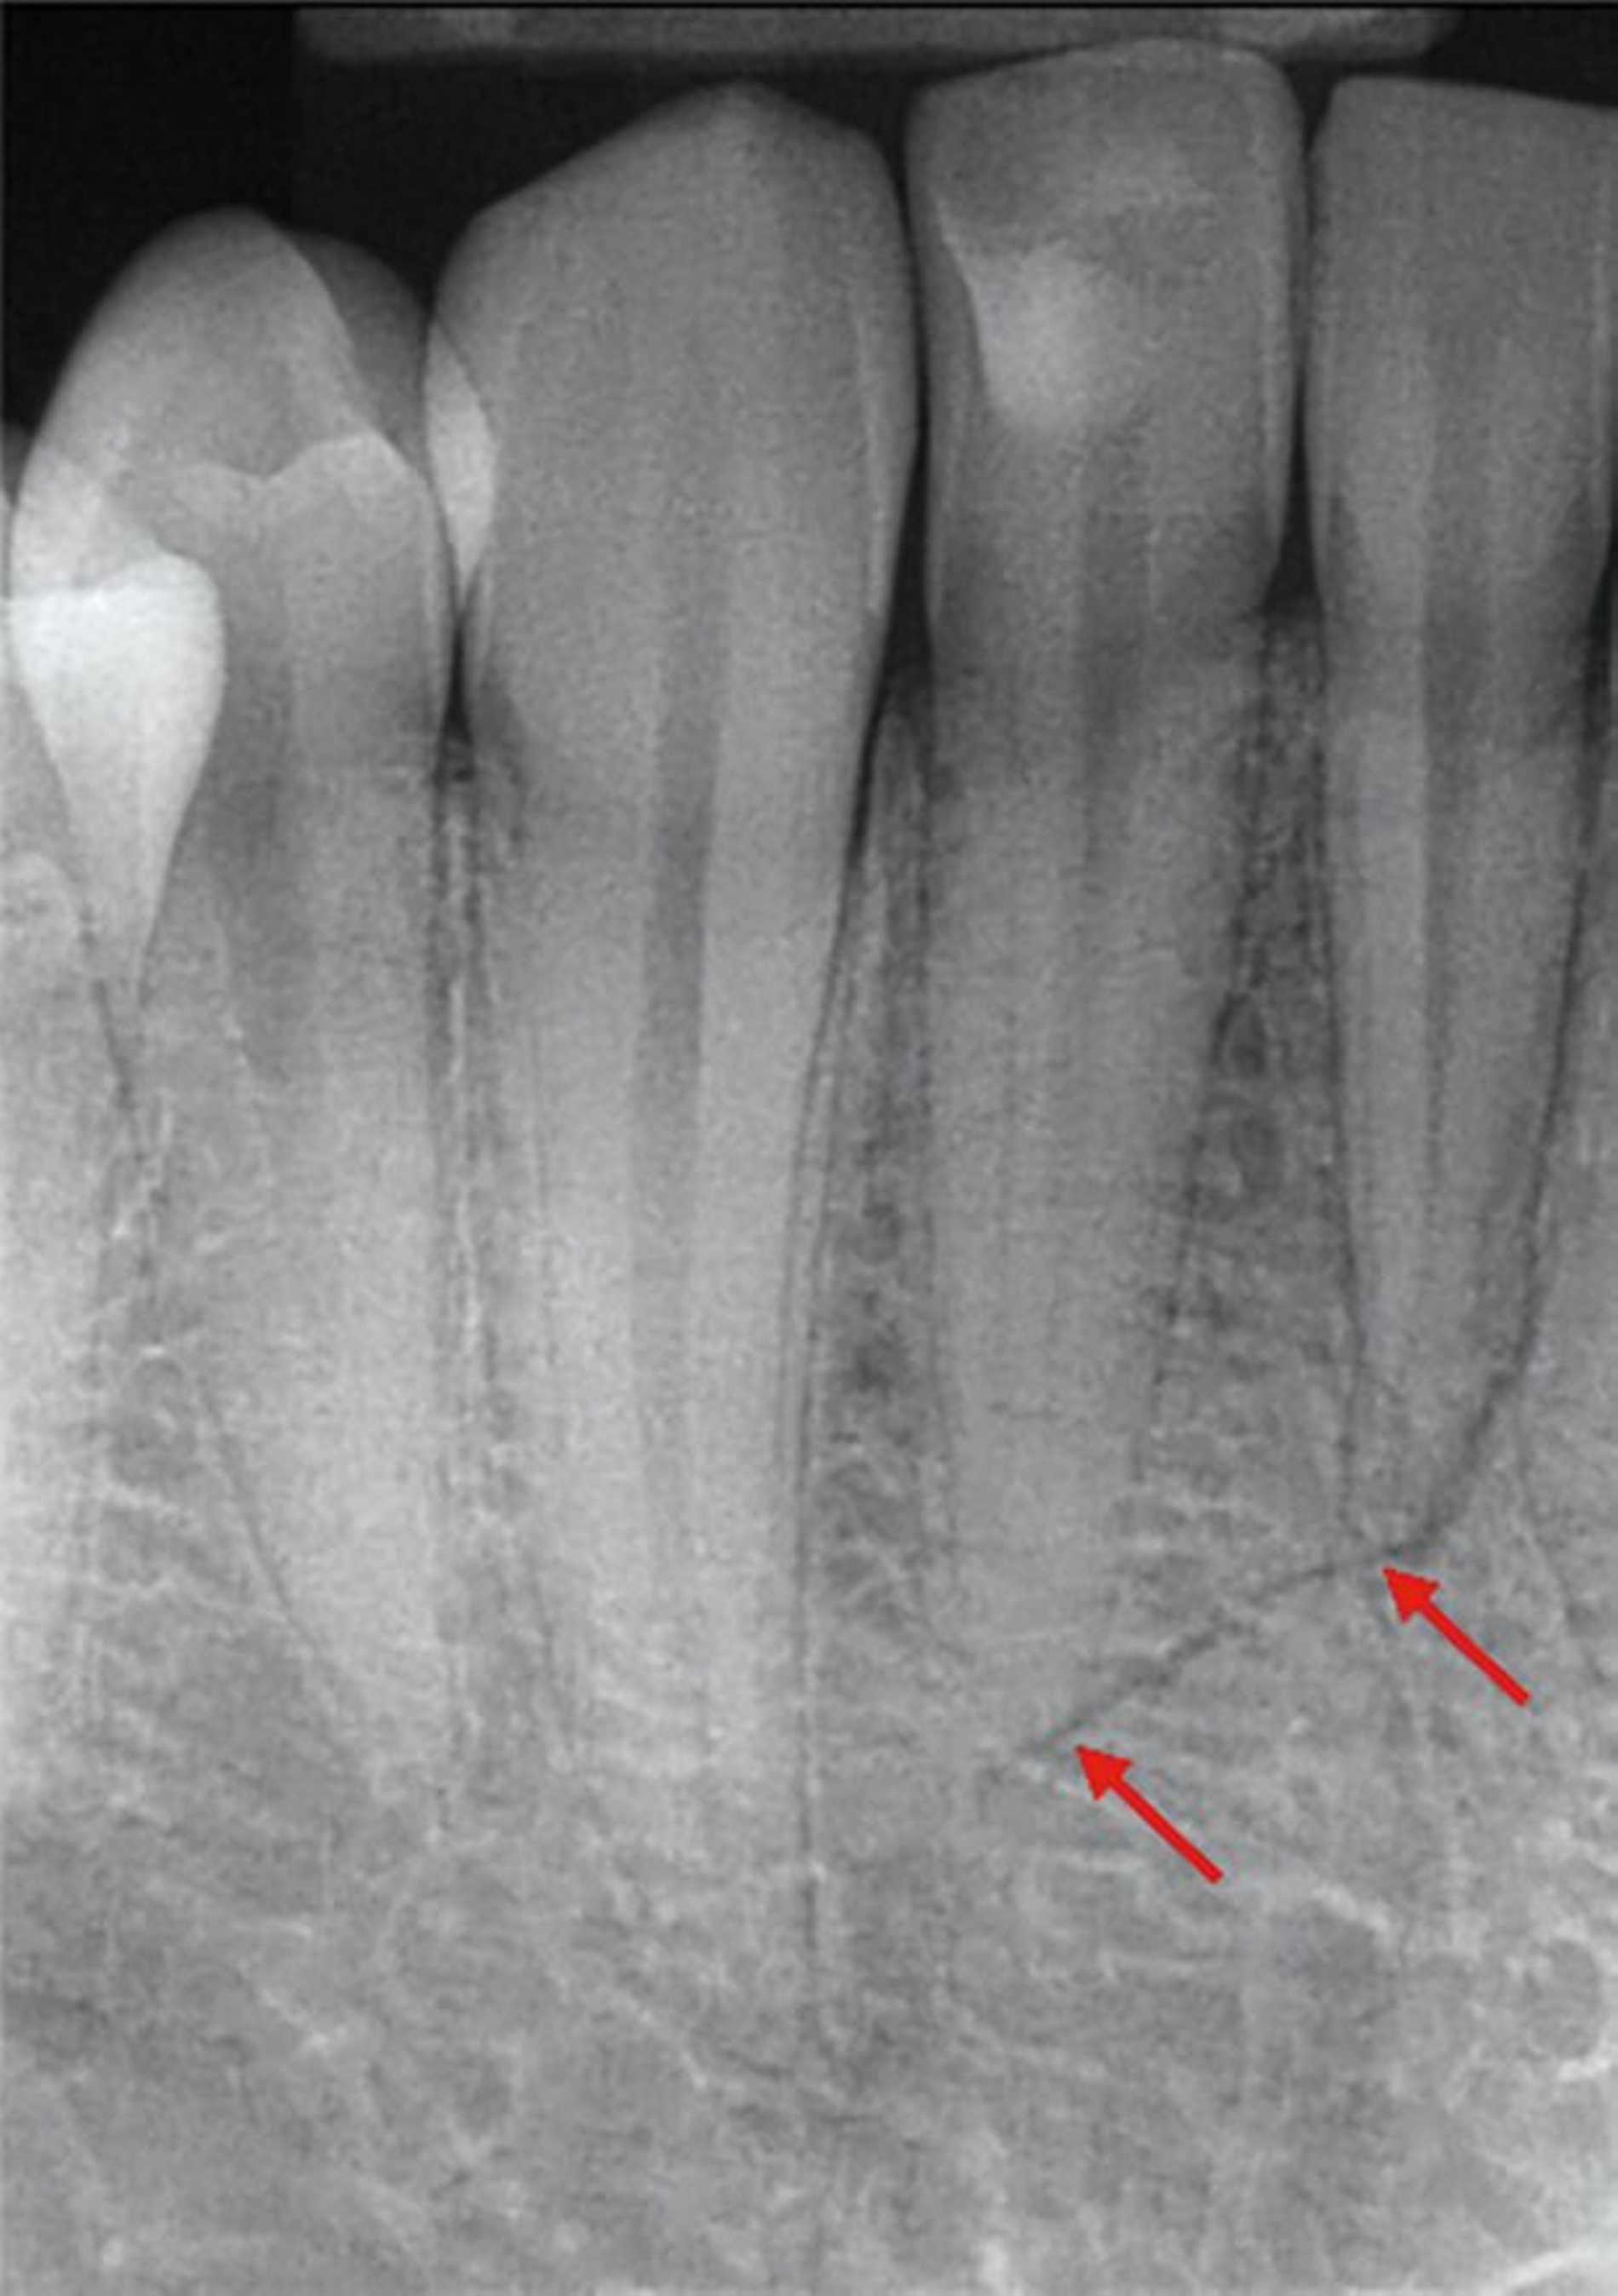

Zunächst wurden Einzelbildaufnahmen der Zähne 24, 26, 35, 33–43 angefertigt. Dabei fiel eine transluzente Frakturlinie ausgehend vom mesialen Parodontalspalt des 41 auf, die sich nach apikal-distal bis zum Apex des 42 darstellte (Abbildungen 3 und 4). Für einen radiologischen Überblick, mit dem auch eine Kiefergelenksfraktur ausgeschlossen werden kann, wurde eine Panoramaschichtaufnahme herangezogen (Abbildung 5). Darauf bildete sich eine unscharfe, C-förmige Transluzenz apikal der Zähne 31 und 41 ab. Eine genaue Beurteilung war nicht möglich, da der Bereich apikal der Unterkieferfront außerhalb der Bildebene lag. Die Processus coronoidei und condylares stellten sich beidseits unauffällig dar. Die Verdachtsdiagnose lautete: Unterkieferfraktur, unkomplizierte Kronenfrakturen an den Zähnen 26 und 35 sowie eine Längsfraktur an Zahn 24.